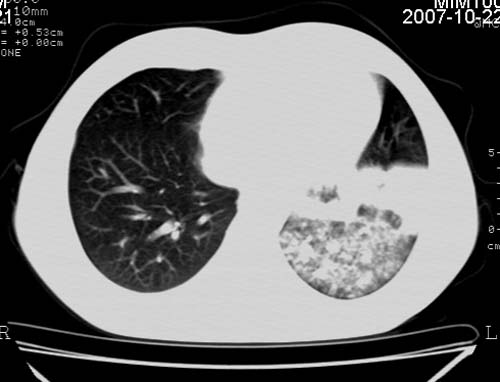

男,21岁,咳嗽、胸闷、乏力伴多汗二十余日、无明显发烧。患者一般情况好,为初三学生。

右肺上叶前段及左肺下叶多形性病变伴厚壁空洞,周边示树芽征.左肺下叶不张改变.

考虑;肺结核,不除外左肺下叶支气管内膜结核.

双肺继发性肺结核伴左侧空洞形成!不除外合并霉菌感染!(双肺多发病灶,左侧病灶形成空洞,并空洞内见壁结节。建议改变体位,观察空洞内结节情况,以便排除霉菌感染!)